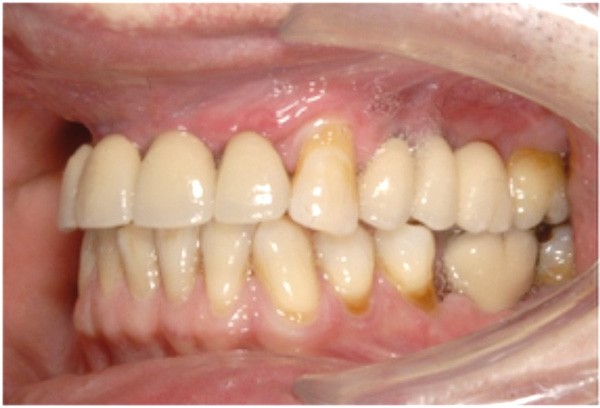

Cette partie de la présentation ne se contentait pas de rapporter les principes précédemment décrits à des régions limitées des maxillaires mais étendait la discussion à la difficulté majeure rencontrée en implantologie : rattraper des erreurs de positionnement implantaire ayant entraîné des compromis prothétiques inesthétiques. La solution thérapeutique mise en œuvre par Benoît Philippe consiste à appliquer la procédure d’ostéotomie segmentaire à l’entité constituée par l’os alvéolaire péri-implantaire et les implants. Les couronnes implantaires sont déposées. Le tracé d’ostéotomie encadre le segment à repositionner mais n’implique pas la corticale palatine qui sera fracturée pour éviter toute lésion du périoste (nourricier du segment alvéolo-implantaire). Un dispositif prothétique préparé en amont guide la translation du fragment qui est fixé au moyen de plaque d’ostéosynthèse dans la situation idéale. Le capital squelettique est reconstruit et l’espace prothétique disponible est normalisé.

Au cours de la conférence, Benoît Philippe a énoncé ses convictions concernant les conditions de succès du traitement implanto- prothétique : le respect d’une biomécanique implantaire équilibrée, le recours à des implants plus fins et moins nombreux que ne l’imposaient les préconisations d’autrefois, l’observation du biotype parodontal plus ou moins favorable aux reconstructions des atrophies étendues, la nécessité de restaurer au préalable puis de maintenir un environnement parodontal satisfaisant (en particulier la gencive attachée péri-implantaire).